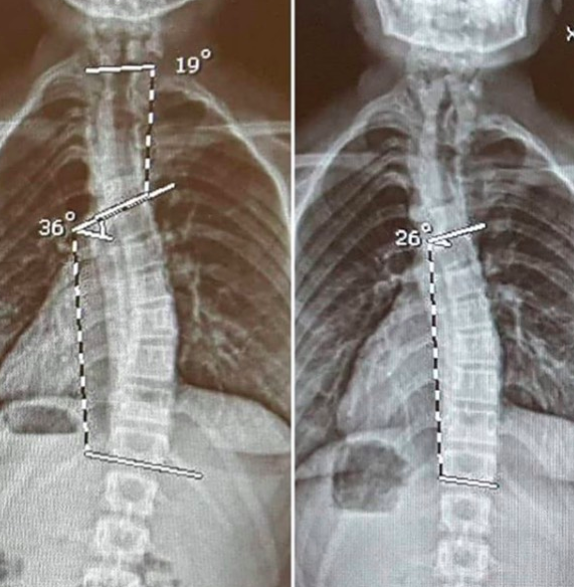

THIS HAPPENED! 10% IMPROVEMENT!! Wow amazing! Although, still a long way to go! This goes to show when you choose the right method and are committed to the cause there is always hope. It’s like that in life too, we feel like our progress is so slow but when you look at how far you’ve come then it makes all the difference.